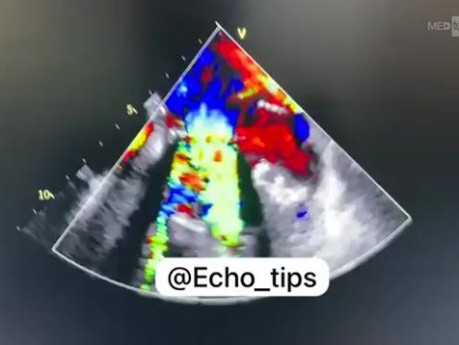

Duży przeciek okołozastawkowy wokół mechanicznej...

Ten film przedstawia duży przeciek okołozastawkowy wokół mechanicznej zastawki mitralnej.